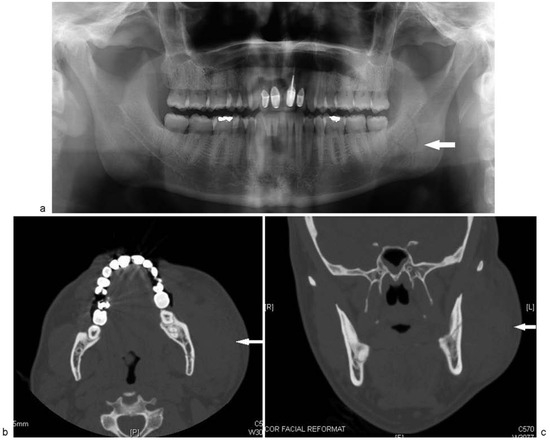

The patient failed to return for 1 week follow-up and was seen 5 weeks postrepair. At this follow-up visit, the patient reported that he began to notice a fluctuant swelling several days following the injury as the surgical edema progressively resolved. He reported that the mass had not increased or decreased in size since he first noticed it. A 4 × 5 cm sized fluctuant swelling was noted over the left ascending ramus of the mandible. The mass was nontender to palpation. The patient was prepped and draped in a sterile fashion. The mass was aspirated percutaneously with an 18-gauge needle producing 20 mL of clear/yellow fluid (Figure 4a–d). A pressure dressing head-wrap was applied. Laboratory analysis of the fluid revealed an amylase value greater than 100,000 U/L. Aerobic and anaerobic cultures were negative.

Figure 4. (ad) Fluctuant left facial mass 5 weeks post-op. Aspiration of 20 mL of fluid from the mass. (d) Post-aspiration.